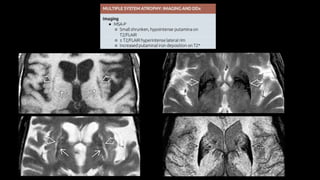

Atrofia de múltiplos sistemas

• Síndrome Parkinson Plus

• Atrofia de múltiplos sistemas (mais comum)

• Paralisia supranuclear progressiva

• Degeneração corticobasal